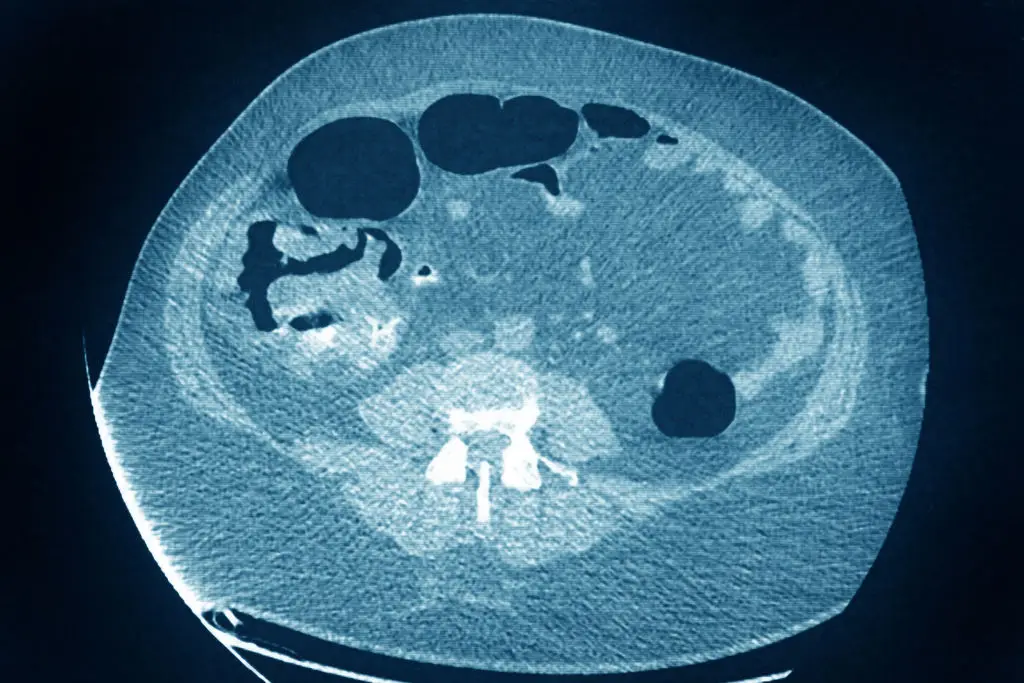

One of the more dangerous forms of cancer is found in the colon, otherwise referred to as colorectal cancer, as it is not only challenging to spot in the early stages of development, but it is challenging to deal with once it grows with a roughly 10 percent survival rate at that point.

Examining 100 long-distance runners between the ages of 35 and 50, Cannon discovered that 39 had developed a form of precancerous tumor in their colon, with the cancer taking an advanced form for 15 of that 39.

This represents a far higher percentage than the expected rate of 1.2 percent – albeit from a comparatively small sample size – leading some to speculate why this might be the case.